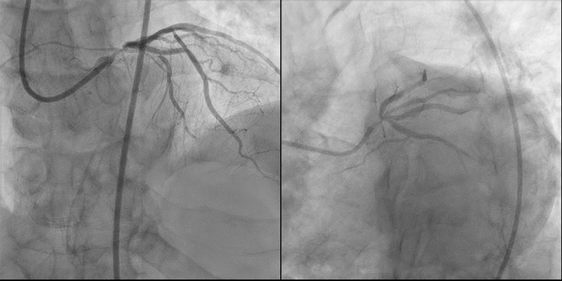

患者术前部分影像学资料

与2017年11月相比,老人的病情有了进一步发展。当日冠脉造影见左主干中段至远段狭窄95%,前降支开口狭窄80%,而且中段发出第一对角支后狭窄95%。葛雷解释道,“左主干相当于是水龙头的总开关,如果有严重的狭窄,一部分患者可能会因此出现心绞痛,一部分患者可能会猝死,还有一部分患者可能会出现心衰。”

一波三折的手术过程。冠脉造影显示,患者左主干狭窄程度在95%,因此首先要让导引钢丝要通过非常严重的狭窄,但患者左主干和前降支之间角度非常大,葛雷介绍说,“首选的常规导引钢丝未能通过左主干严重狭窄的病变处进入狭窄的前降支血管。”